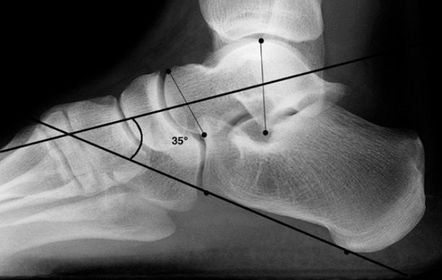

| What is this angle called? What foot type does it indicate? | Talar - 1st MT or Meary's Angle Pes plano-valgus |

| What is this angle called? What foot type does it indicate | Talar - 1st MT or Meary's Angle Pes cavo-varus |